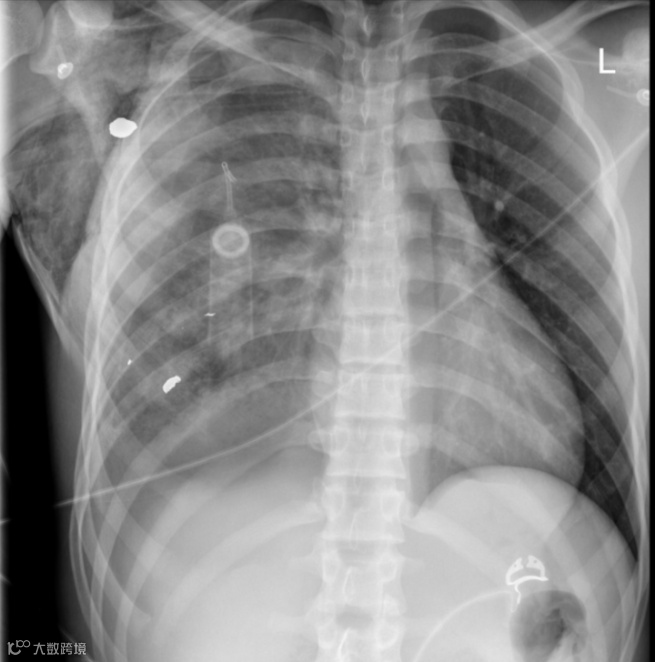

男,17岁,右侧胸腔遭枪击后,右侧胸部高密度子弹碎片,右胸腔中度血气胸,海姆立克瓣膜胸腔引流术后,伴有皮下气肿,纵隔左移。